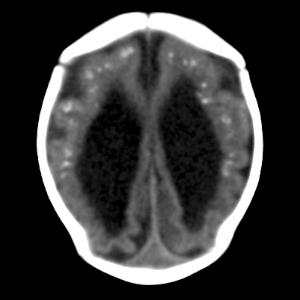

Though much of the concern in the media regarding the toxic effects of Zika virus has focused on brain findings of microcephaly, the researchers noted that there are a variety of brain abnormalities that can be found in fetuses exposed to the virus, including gray and white matter volume loss, brainstem abnormalities, calcifications, and a condition called ventriculomegaly, where the ventricles, or fluid filled spaces in the brain, are enlarged. Some babies infected by Zika may not have a small head size if the ventricles remain excessively enlarged.

The brain abnormalities seen in confirmed and presumed Zika groups were very similar. Nearly all of the babies in each group had ventriculomegaly. Although most fetuses had at least one exam showing abnormally small head circumference, the researchers discovered that head circumference was normal in three fetuses with severe ventriculomegaly.

The babies' skulls frequently had a collapsed appearance with overlapping sutures and redundant skin folds. The researchers believe the unusual appearance of the skull is due to a combination of the small brain as it develops, but also a result of what at some point was likely a larger head size—due to ventriculomegaly—that then decompresses, and/or brain atrophy, giving the skull the collapsed shape.